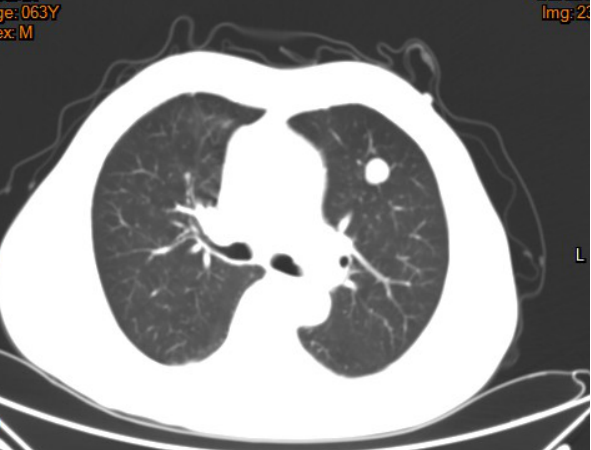

影像学资料:

2017年3月

2017年7月

2018年2月

2018年3月